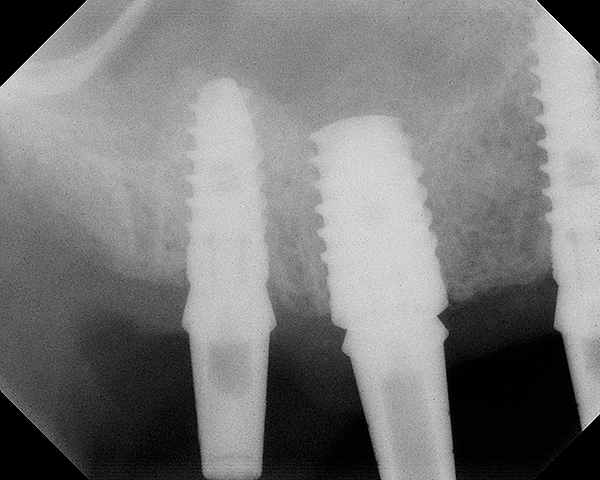

Fig 19. CBCT scan (Kodak 9000D) of implant No. 14 showing homogeneous appearance of the bone.

Figure 19